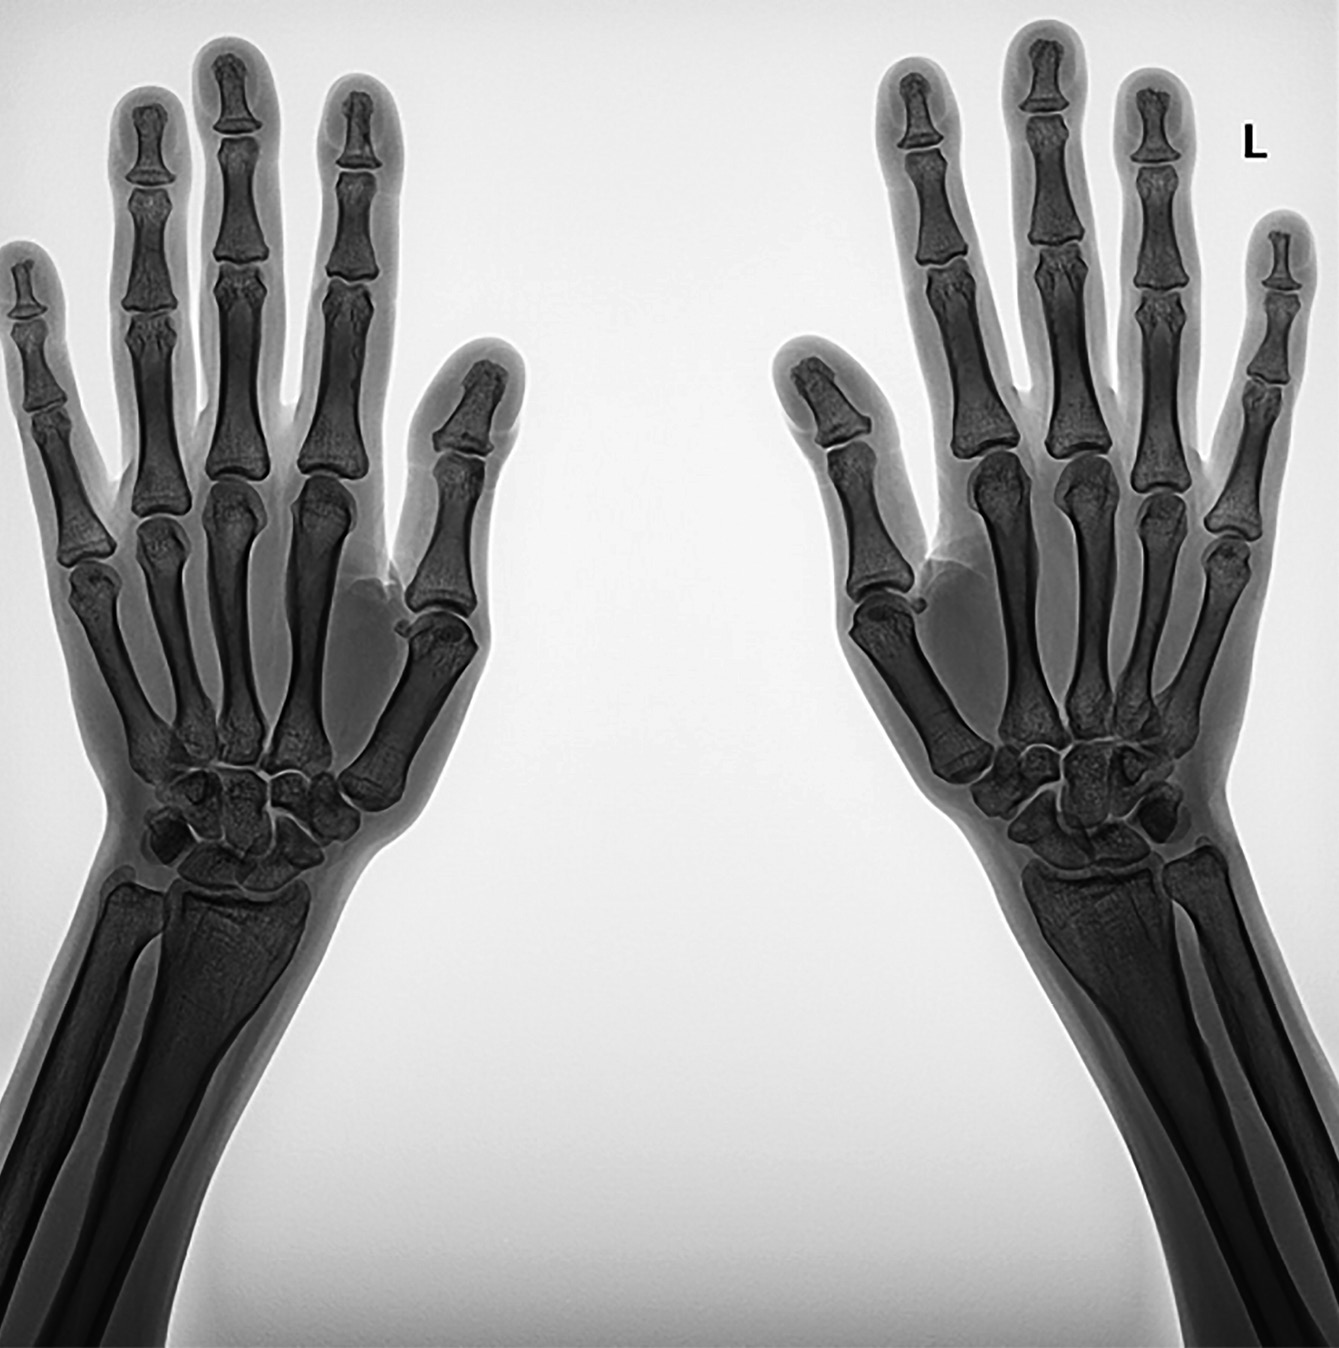

По результатам рентгенографии кистей рук отмечены гипертрофия эпифизов ногтевых фаланг, акроостеолиз, гиперпериостоз диафизов пястных костей и костей предплечья (рис. 3). При проведении рентгенографии коленного сустава выявлены выраженный периостоз диафизов бедренных костей (толщина надкостницы 0,98 cм), средневыраженный периостоз диафизов большеберцовых костей, утолщение внутреннего кортикального слоя надколенника до 0,41 см (рис. 4). По данным рентгенографии голеностопного сустава также отмечаются средневыраженный периостоз, повышение плотности кортикального слоя, гипертрофия пяточного бугра, повышение толщины мягких тканей стопы до 2,72 см слева, гипертрофия задней малоберцовой мышцы, утолщение периоста в нижней трети диафиза малоберцовой кости до 0,85 мм справа и до 0,77 мм слева (рис. 4).

Рисунок 3. Рентгенография кистей рук пациентки Х.

Примечание. Гипертрофия эпифизов ногтевых фаланг, акроостеолиз,

гиперпериостоз диафизов пястных костей и костей предплечья.